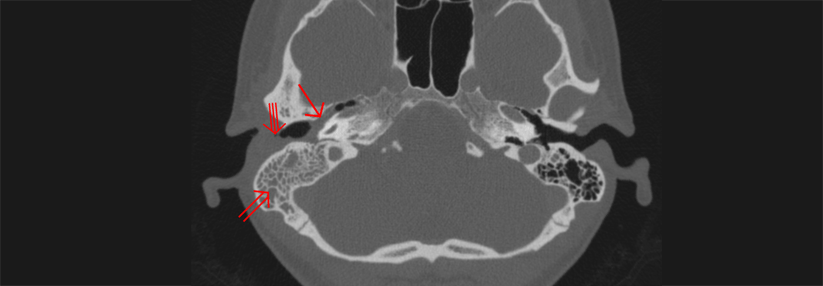

Die akute Otitis media betrifft vor allem Vorschulkinder, meist als Begleiterscheinung einer Infektion der oberen Atemwege. Die Diagnose erfolgt per Otoskopie, die Behandlung in erster Linie mit Analgetika. Antibiotika sind nur in bestimmten Situationen erforderlich.

Einer Otitis media geht meist ein Infekt der oberen Atemwege voraus, der das Mikrobiom in Nase und Rachen stört. Das ebnet pathogenen Bakterien den Weg, sodass diese über die Eustachi-Röhre ins Mittelohr gelangen und dort eine Infektion auslösen können, schreiben Dr. ­Roderick ­Venekamp von der Universität ­Utrecht und Kollegen. Junge Kinder sind besonders anfällig für akute Mittelohrentzündungen, da einerseits ihre ­Tuba ­auditiva kürzer und weiter ist als bei älteren und andererseits die Funktionen des kindlichen Immunsystems noch nicht ausgereift sind. Bis zum dritten Geburtstag erleidet die Hälfte der Kinder im Durchschnitt drei Mittelohrentzündungen.